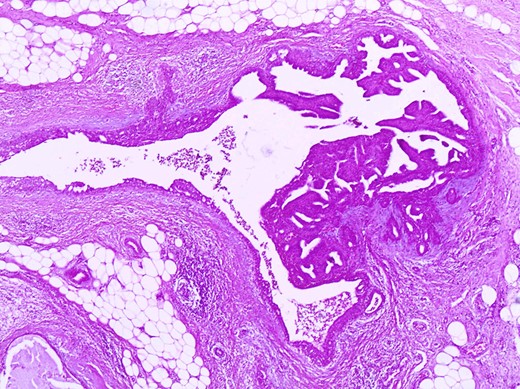

The histologic examination revealed an intraductal papilloma of 9 mm in maximum diameter with no evidence of atypia or malignancy (Figs 3,4 and 5).

Immunohistochemistry with CK14 demonstrates the myoepithelial cells in the papillary structures (CK14×200).